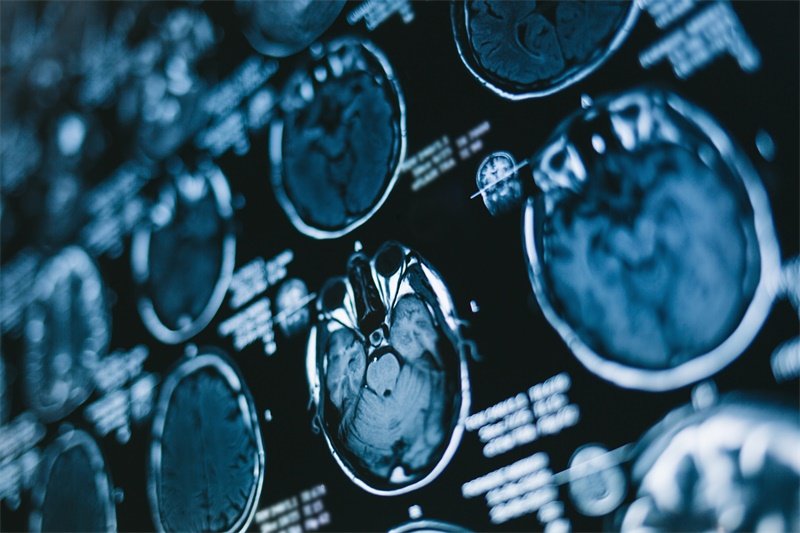

影像学检查在左侧大脑镰旁占位性病变的诊断中至关重要。常见的影像学检查手段包括

MRI 是评估大脑组织病变的金标准,能够清晰显示占位性病变的细节。通过 T1 和 T2 加权成像,医生可以观察到病变的信号强度及边界特征。通常,肿瘤表现为高信号或者低信号区域,这与其性质密切相关。

弥散加权成像(DWI)是一种高敏感度的MRI技术,特别适合用于探测缺血性病变和肿瘤。通过该成像方法,能够判断细胞组分的变化,进而为疾病的分型提供支持。